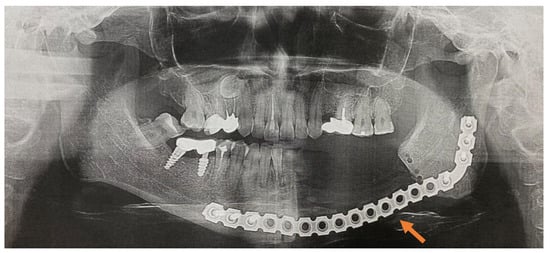

In total, 82 patients were interviewed of which 39 (47.6%) patients were in the control group and the main group included 43 patients who (52.4%) underwent radical surgical treatment (Figure 1a–d). The mean age of the patients in both groups was 66.8 ± 10.03 years. As regards the localization of the primary site of cancer, patients with a history of malignant neoplasm (MN) of the prostate prevailed, followed by MN of the breast (Table 1 and Table 2).

The patients in the main group (43 subjects) underwent segmental resection of the jaw after preoperative preparation (Figure 2 and Figure 3a,b).

An analysis of the results obtained from the Numeric Pain Rating Scale demonstrated that the mean pain intensity before treatment was 8.9 points in the control group, and 9.7 in the main group (Figure 4). These values are indicative of “unbearable pain.” After treatment (30 days), the pain score in the control group decreased and amounted to 4.1; this is evidence of the persistence of “moderate pain” in the patients. In patients who underwent segmental jaw resection (Figure 5a,b and Figure 6), the mean pain intensity was 0.5. There was no relationship with gender, but there was a direct relationship between the intensity of the pain and the stage of the process (CI = 95%).

Figure 1. (ad) Patient A: 47-year-old female. DS: Medication-related osteonecrosis of the jaw (the left side). Surgical treatment: Resection of the lower jaw on the left (9 September 2018).

Figure 3. (a,b) CT scan before operation (26 April 2018).